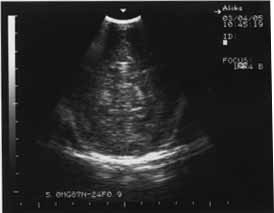

У остальных новорожденных, из группы детей получающих Лецитин, выявлена положительная ультразвуковая динамика процесса в головном мозге в виде уменьшения эхоплотности в перивентрикулярном пространстве, которое свидетельствовало об ишемическом страдании. Структуры мозга становились более четкими, а к концу первого месяца жизни исчезали очаги глиоза и мелкие кисты, нивелировались участки уплотнения борозд (рис. 3,4,5,6,).

Рис 3. В начале лечения новорожденная С. 34 недели гестации, эхоплотность повышена, структуры нечеткие, мелкие очаги глиоза в паренхиме. | Рис. 4. Через 20 дней от начала лечения. Уменьшение эхоплотности в п/в пространстве. П/в ишемия II ст. (не выражена) |

Рис. 5 Срок гестации 28 недель. | Рис.6. На 10-е сутки от начала лечения. В динамике отмечается уменьшение интенсивности п/в ишемии. |